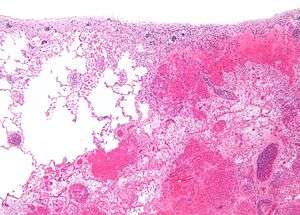

| Micrograph of a pulmonary infarct (right of image) beside relatively normal lung (left of image). H&E stain. | |

- Red infarctions (hemorrhagic infarcts), generally affect the lungs or other loose organs (testis, ovary, small intestines). The occlusion consists more of red blood cells and fibrin strands. Characteristics of red infarcts include: